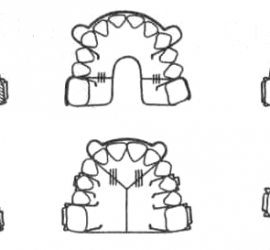

Цемент поликарбоксилатный (ТУ 64-2-275-78) выпускается Харьковским производственным объединением «Стома» (Украина). Предназначен для пломбирования молочных зубов и временных пломб, в качестве прокладок под постоянные пломбы из амальгамы, пластмассы и силикатного цемента, а также для фиксации вкладок, различных видов коронок, небольших мостовидных протезов и ортодонтических аппаратов. Поликарбоксилатный цемент выпускается в виде комплекта […]